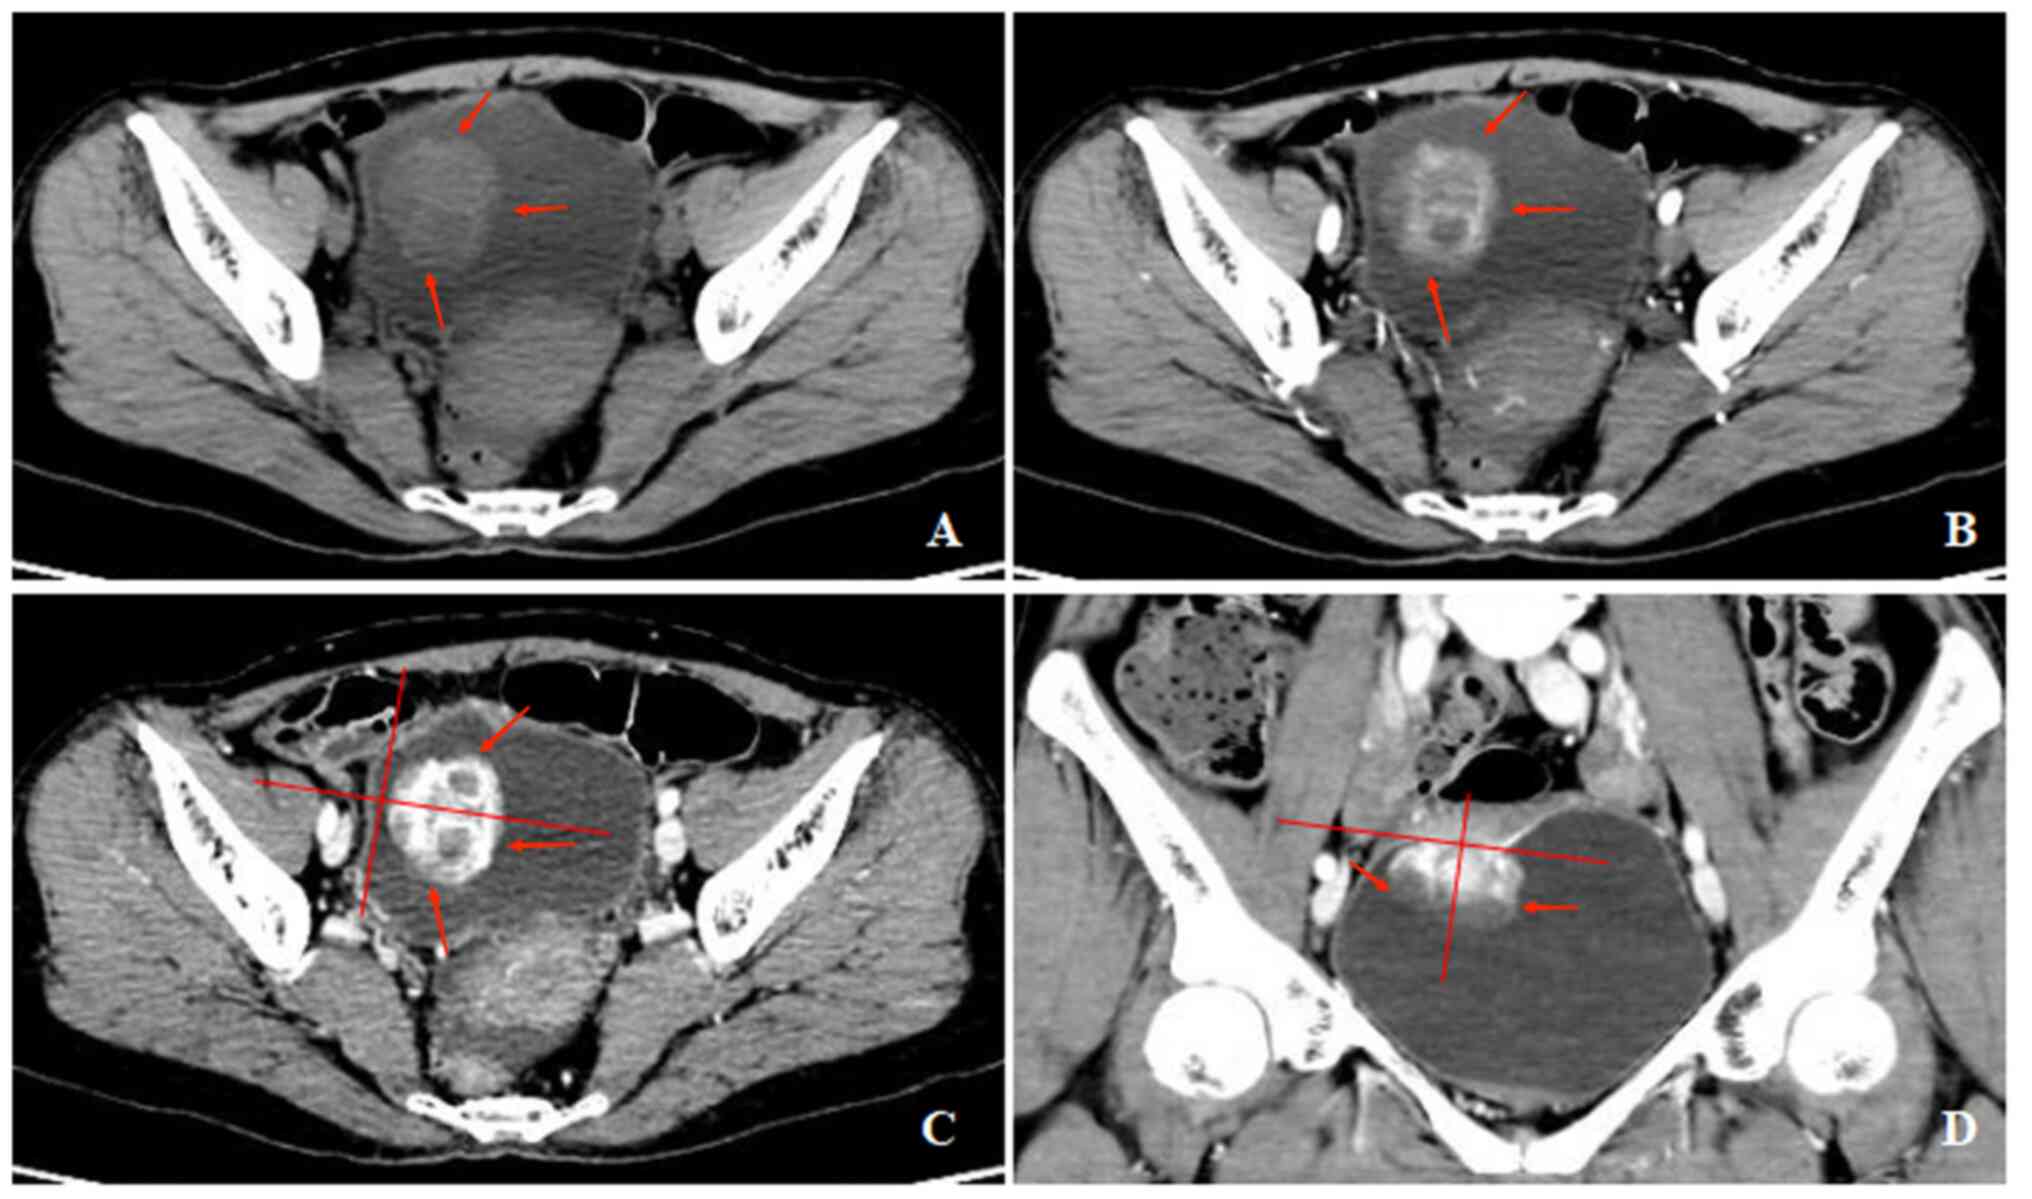

Figure 4

A 35-year-old man with gross hematuria, frequent urination, irregular blood clot. (A) Unenhanced CT scan of bladder showed a limited thick-walled with a mixed growth pattern on the front wall, with homogeneous density. (B and C) Contrast-enhanced CT scans revealed heterogeneous enhancement of the lesion.

The CT findings showed that 8 (89%) patients had one tumor and 1 (11%) patient had multiple tumors. The bladder IMT size ranged from 1.3x2.1 to 4.8x5.1 cm2. Tumors occurred in the posterior wall in 2 (22%) patients, 5 (30%) patients had tumors occurred in the superior wall, 1 (11%) patient had tumors occurred in the front wall, and 1 (11%) patient had tumor occurred in the left wall (Fig. 2, Fig. 3, Fig. 4 and Fig. 5). An endophytic growth pattern (Fig. 3) was identified in 4 (44%) patients, an exophytic growth pattern (Fig. 2) was observed in 2 (22%) patients, and a mixed growth pattern (Fig. 5) was revealed in 3 (33%) patients. The tumor manifests morphologically as either polypoid (n=5), or cauliflower-like (n=1) soft-tissue mass with a wide base in the cavity, or a limited thick-walled (n=3) in the bladder. The tumor margins were smooth (n=8) or lobulated (n=1) and the tumor boundaries were either clear (n=7) or ill-defined (n=2).

The unenhanced CT examination of the lesions revealed either low density (n=4), iso-density (n=3), or slightly high density (n=1), and density was either homogeneous (n=3) or heterogeneous (n=6). The enhanced CT examination of the lesions showed either ring-shaped (n=3) or heterogeneous (n=6), and the degree of enhancement was either significant (n=6), or moderate (n=3). The enhancement pattern was persistent (n=9). In addition, all polypoid and cauliflower-like soft-tissue masses showed a symmetrical change in the center of the lesion after enhancement on the CT image.